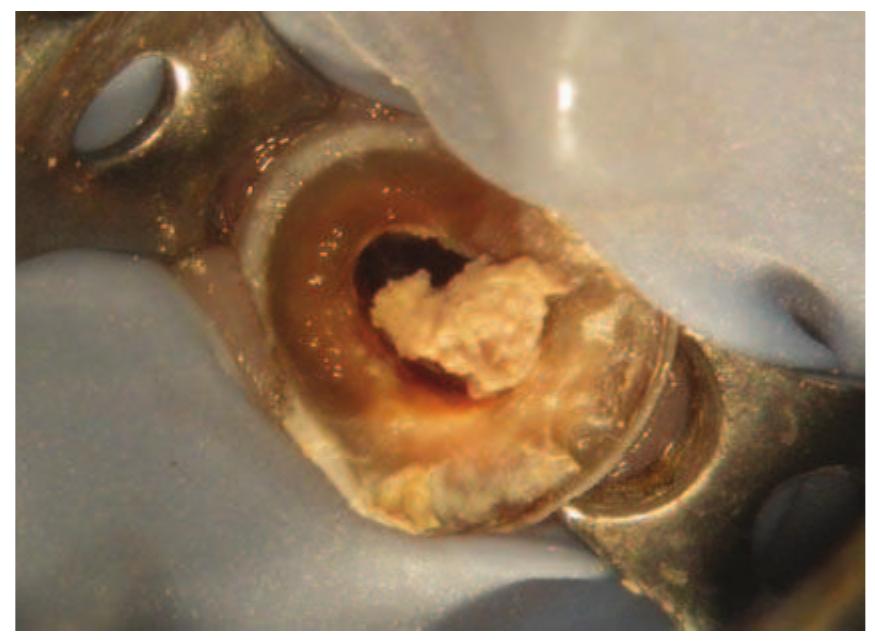

- There is little root filling material present and the root canal would undoubtedly be infected.

- An attempt at root canal treatment has been made but the root canals are extremely fine and have not been successfully negotiated.

- This can then be placed into the root canal.